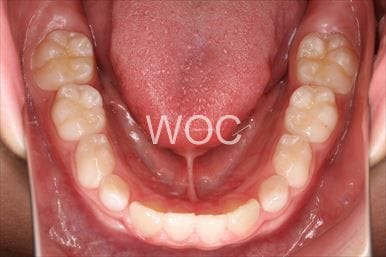

治療前1

治療前2

治療前3

治療前4

治療前5